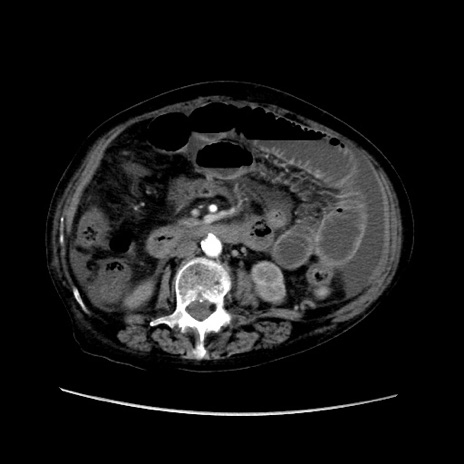

症例31(横断像)

【症例】80歳代 女性

【主訴】腹部膨満感

【現病歴】他院にて肝硬変にてフォロー中。1週間前から便秘、腹部膨満感、臍部腫瘤あり受診となる。

【既往歴】肝硬変

【身体所見】腹部膨隆あり、皮膚変化なし、疼痛なし。

【データ】WBC 4600、CRP 0.25